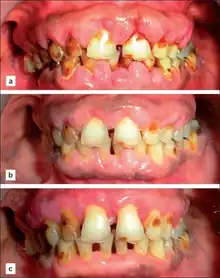

| A severe case of gingivitis | |

The symptoms of gingivitis are somewhat non-specific and manifest in the gum tissue as the classic signs of inflammation:

- Swollen gums

- Bright red or purple gums

- Gums that are tender or painful to the touch

- Bleeding gums or bleeding after brushing and/or flossing

- Bad breath (halitosis)

Additionally, the stippling that normally exists in the gum tissue of some individuals will often disappear and the gums may appear shiny when the gum tissue becomes swollen and stretched over the inflamed underlying connective tissue. The accumulation may also emit an unpleasant odor. When the gingiva are swollen, the epithelial lining of the gingival crevice becomes ulcerated and the gums will bleed more easily with even gentle brushing, and especially when flossing.